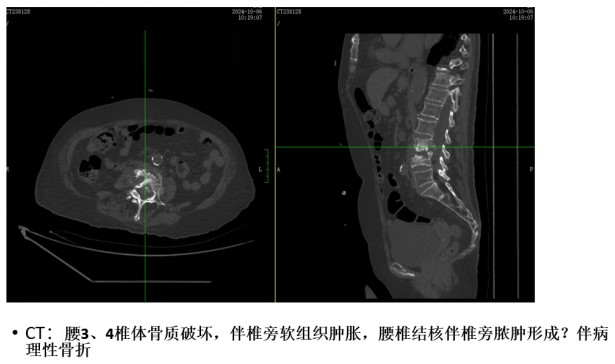

為解決老人病痛,脊柱外科錢軍博士團隊對其進行了詳細(xì)的查體以及全面細(xì)致的評估,診斷為L3、4脊柱結(jié)核伴病理性骨折、椎旁膿腫,患者腰部疼痛癥狀逐漸加重,病灶已經(jīng)壓迫神經(jīng)引起了截癱。